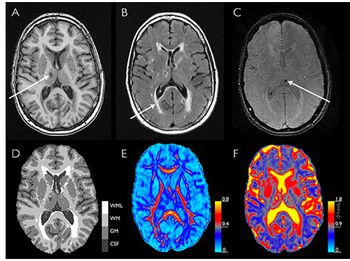

CHICAGO-MRI suggests that subclinical cardiac dysfunction could be indicative of early brain disease.

CHICAGO-MRI shows abnormal cerebral blood flow even if concussed athletes clinically ready to return to sport.